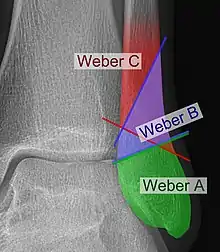

Danis–Weber classification on X-ray.

Fracture of the fibula distal to the syndesmosis (the connection between the distal ends of the tibia and fibula). Typical features:

• below level of the ankle joint

• tibiofibular syndesmosis intact

• deltoid ligament intact

• medial malleolus occasionally fractured

• usually stable: occasionally nonetheless requires an open reduction and internal fixation (ORIF) particularly if medial malleolus fractured

Fracture of the fibula at the level of the syndesmosis. Typical features:

• at the level of the ankle joint, extending superiorly and laterally up the fibula

• tibiofibular syndesmosis intact or only partially torn, but no widening of the distal tibiofibular articulation

• medial malleolus may be fractured or deltoid ligament may be torn

• variable stability

Fracture of the fibula proximal to the syndesmosis. Typical features:

• above the level of the ankle joint

• tibiofibular syndesmosis disrupted with widening of the distal tibiofibular articulation

• medial malleolus fracture or deltoid ligament injury present

• unstable: requires ORIF